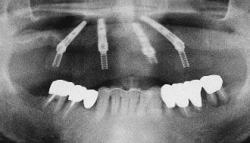

| 治療前 | 治療後 |

|---|---|

| 下顎の前歯部以外の全ての歯にグラツキがあったため、上顎はAll-on-4、下顎の奥歯は通常のインプラントブリッジとしました。 | |